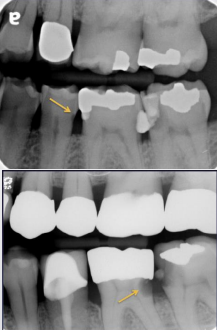

top arrow, classify this lesion based on the ADA caries classification system

D1

bottom arrow, classify this lesion based on the ADA caries classification system

D2

classify this lesion based on the ADA caries classification system

D3